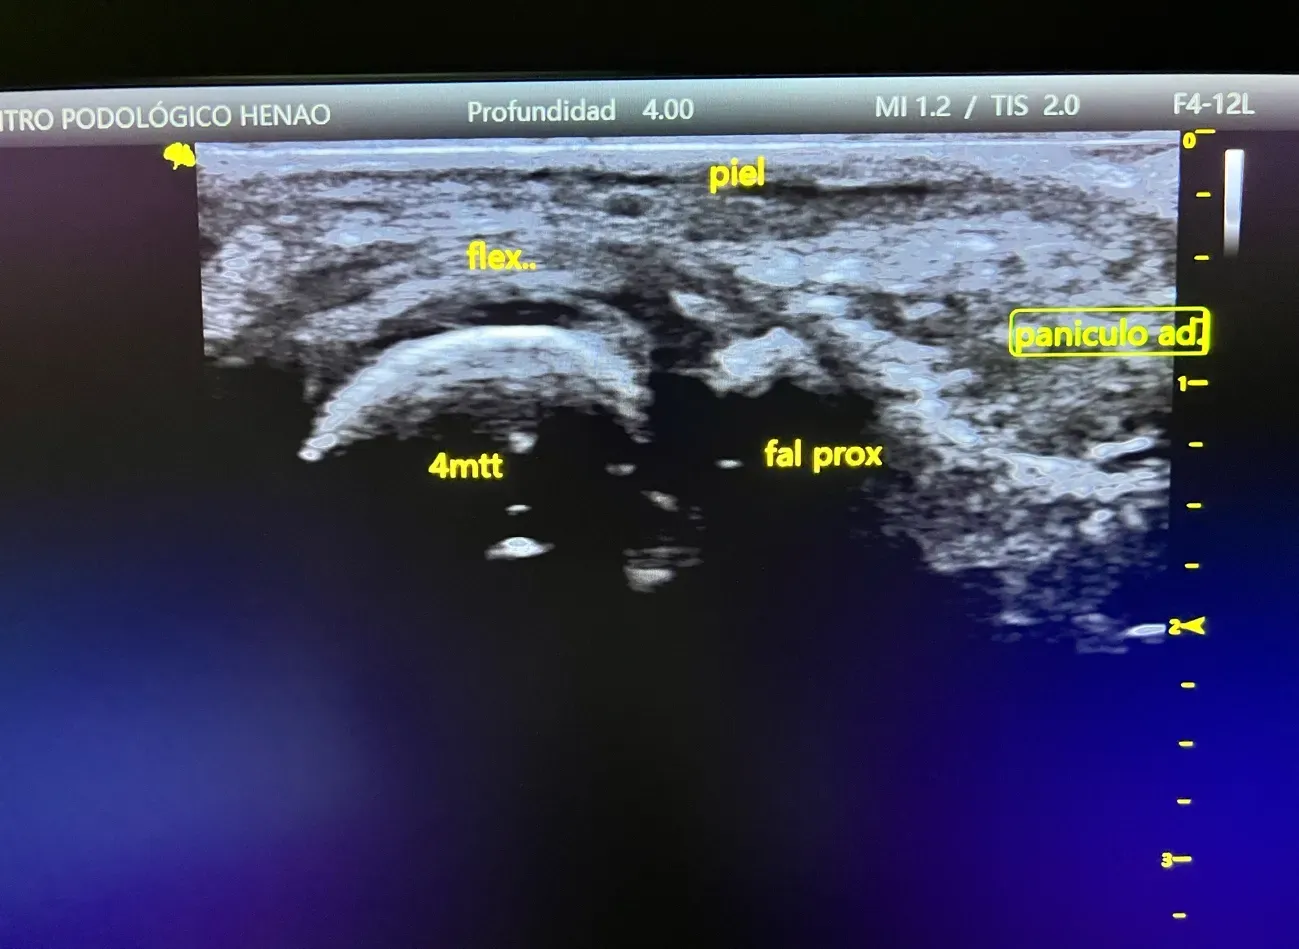

Ecografía musculoesquelética

La ecografía podológica nos permitió valorar las estructuras internas del pie de forma no invasiva.

Metatarsalgia bilateral por sobrecarga mecánica, en paciente con diabetes mellitus, asociada a alteración biomecánica del apoyo (pie equinizado), atrofia del panículo adiposo plantar e hiperpresión mantenida en metatarsianos menores.